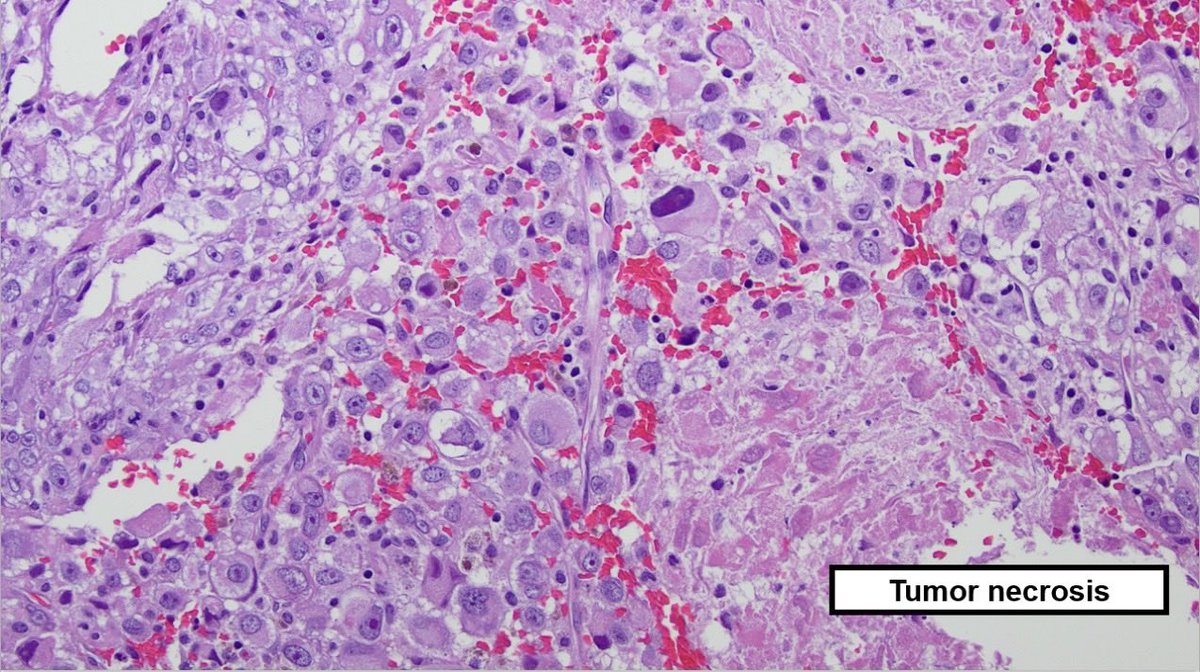

I’m honored to be the winner of #ASCP2021 research abstract in Education Practice category ☺️ THANK YOU VERY MUCH! Dr. Borkowski @tampapath and team for all your support and guidance! ☺️ bit.ly/3jQIHRP @USFpathology @ChampeauxMD @EHJPathDiva @NRiddleMD